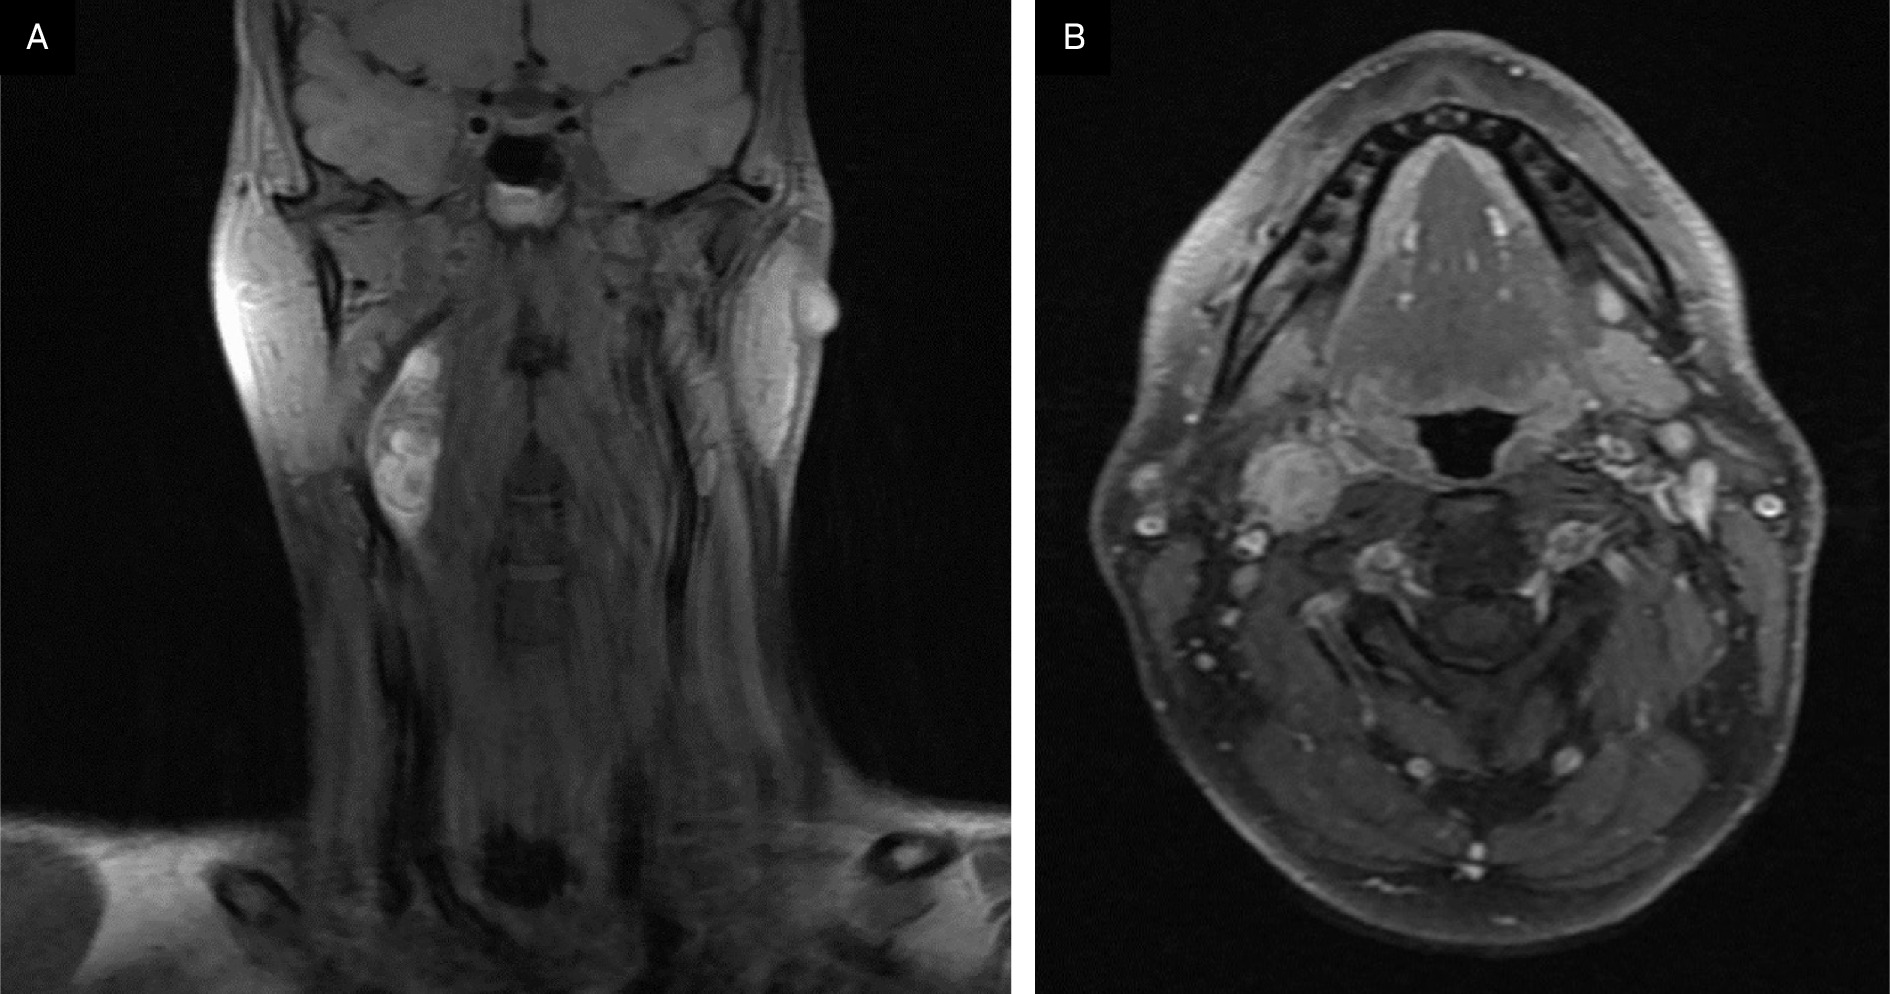

A contrast-enhanced CT neck was significant for a 3.9 × 1.7 × 1.6 cm heterogeneous, partially calcified enhancing lesion in the right carotid space, splaying the internal and external carotid. The radiological differential included a carotid body tumor, with other etiologies like schwannoma or an enlarged lymph node less likely. An MRI demonstrated a 4 cm enhancing lesion in the right carotid space, similarly suspicious for carotid body tumor and, less likely, schwannoma or pathologic lymph node (Figure 1). A chest/abdominopelvic CT scan was negative for thoracic or abdominal paragangliomas and any metastatic disease. A hypermetabolic lesion in the right upper cervical neck was seen on preoperative PET-CT.

Key imaging features include enhancement at CT and FDG-avidity at PET-CT. It has also been noted that MMNSTs typically grow along a spinal nerve root with a unique “dumbbell” configuration, though this is a nonspecific finding, as many types of tumors assume this configuration if they contain intradural and extradural components.7-9 MRI is useful in distinguishing them from other tumors, as MMNSTs have intrinsic T1 hyperintensity (Figure 1), while schwannomas and neurofibromas tend to be hypointense on T1 and hyperintense on T2.10